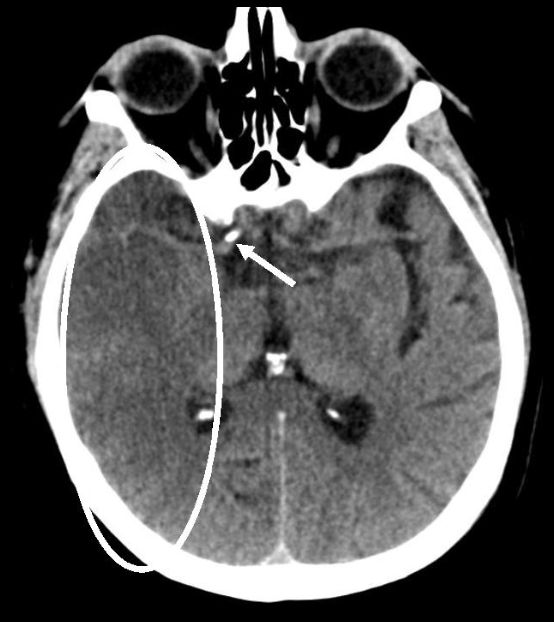

16

Q

A

EVC hemorragico

Hipertensivo